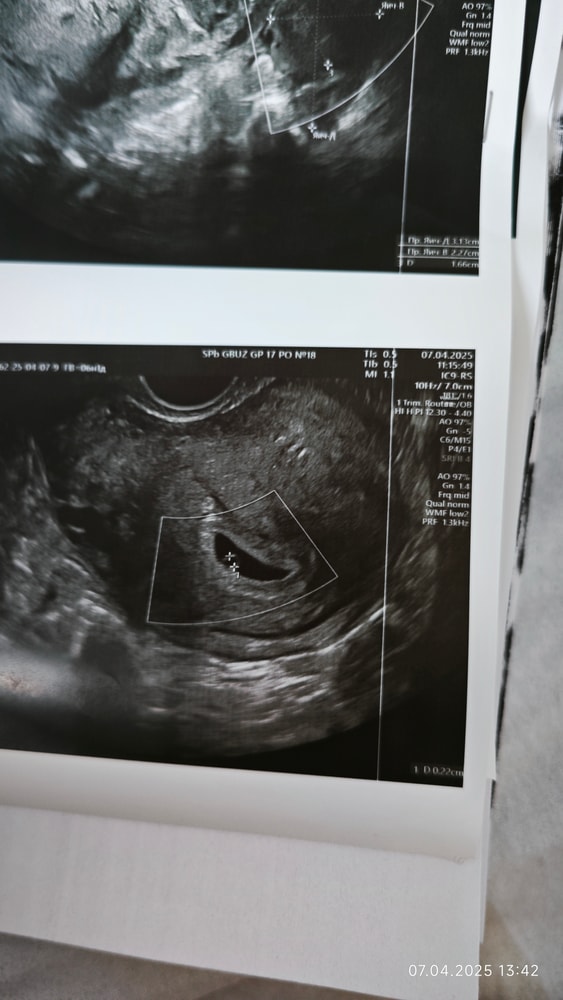

Ставят замершую беременность

Хгч 30.03.25 621,9 на узи ничего нет, хгч 01.04.25 1381 на узи плодное яйцо 4,5 мм. узи 03.04.25 плодное яйцо 7 мм, желточный мешок